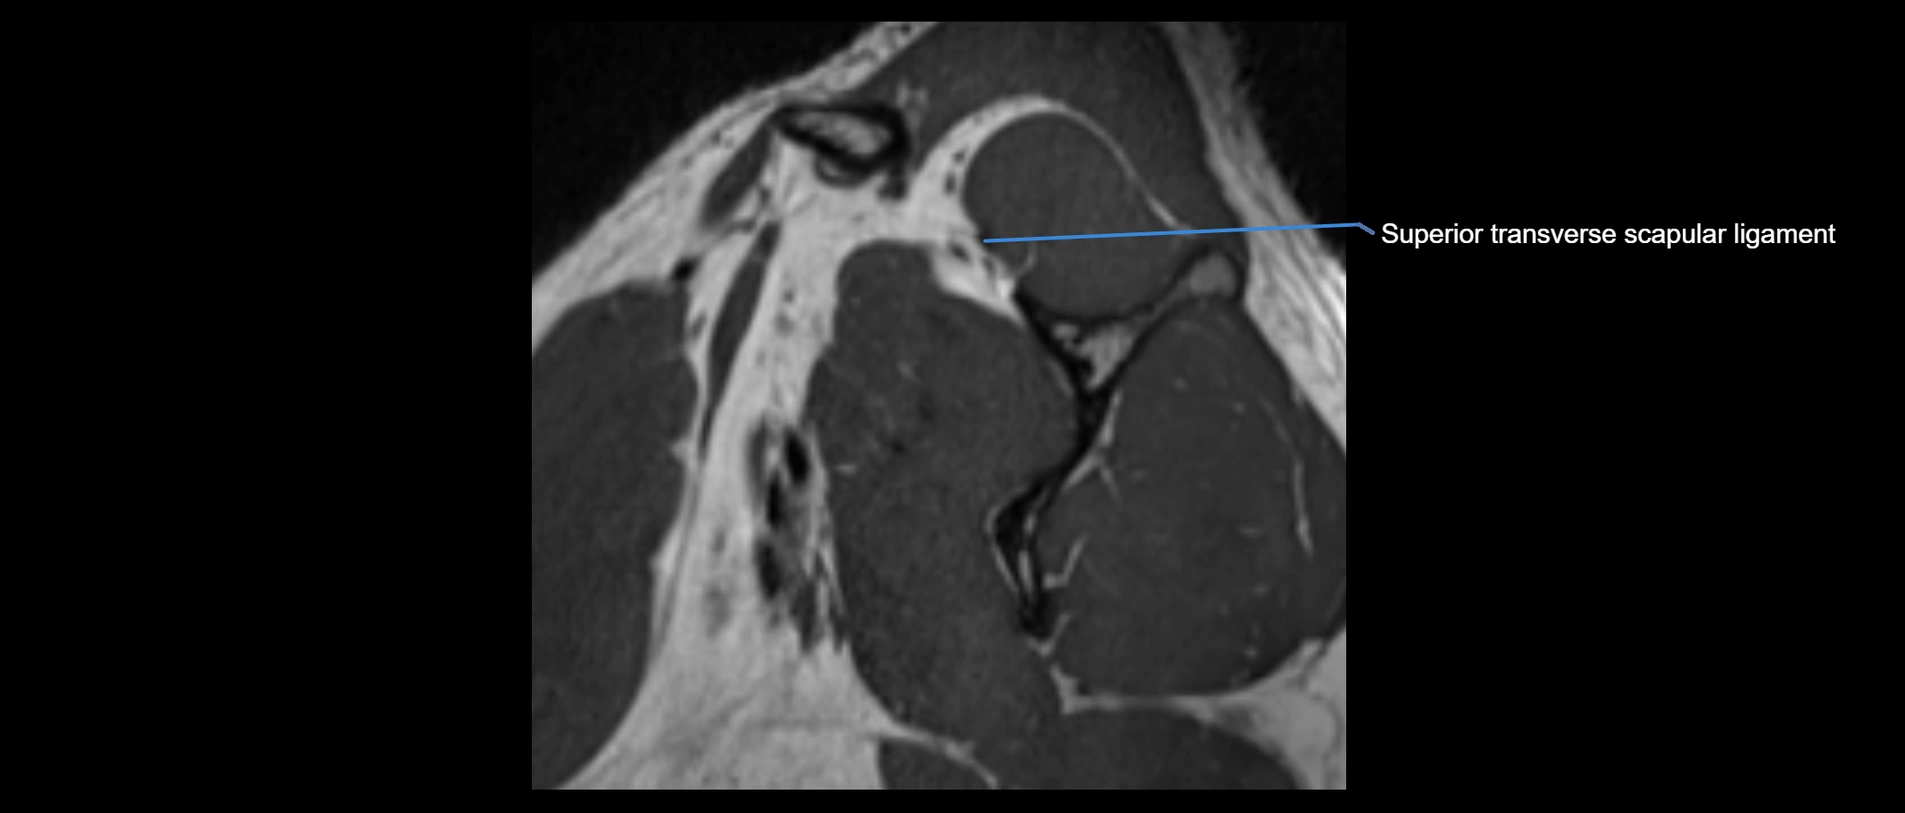

CT image

image